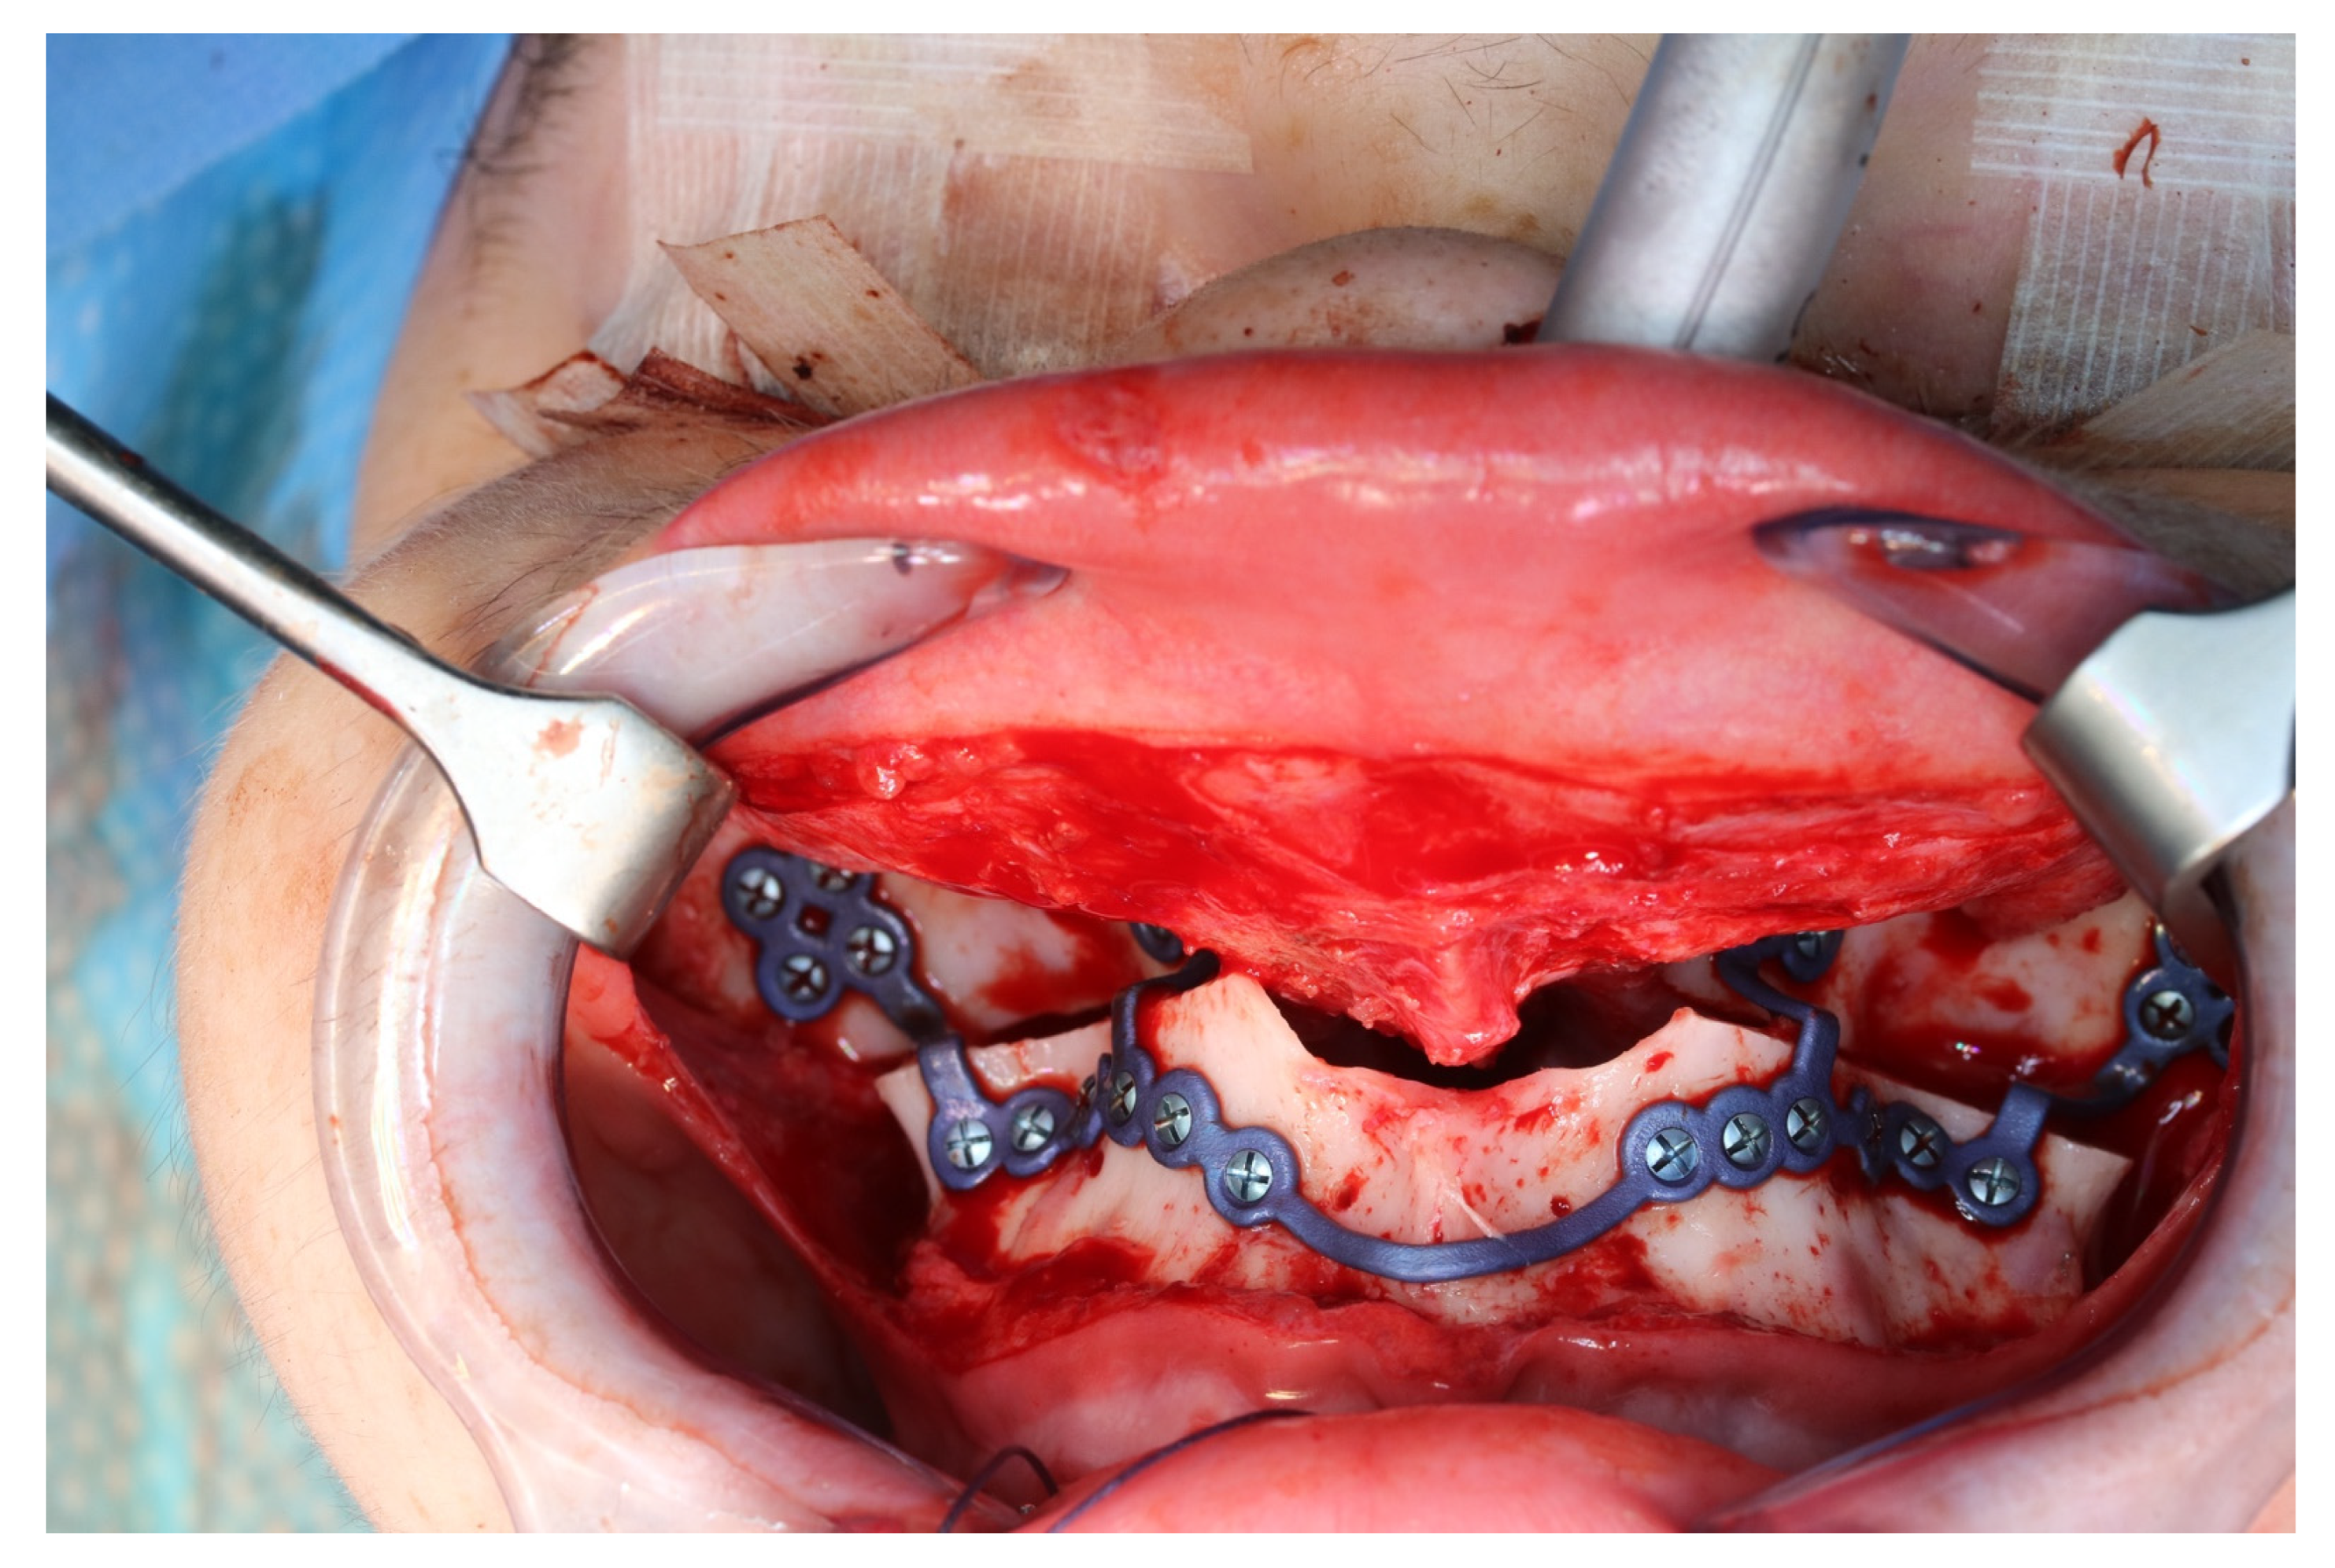

Figure 11.

Upper jaw positioned and fixed by means of patient-specific implant.